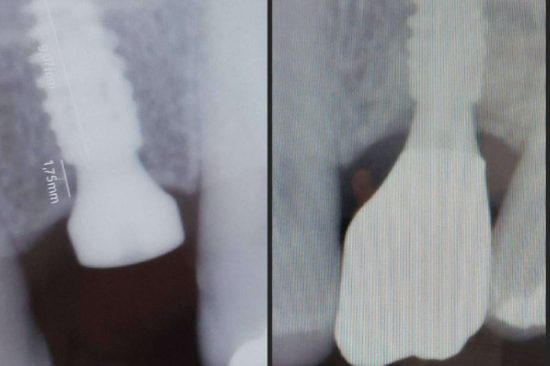

El primer paso para que una persona recupere su dentadura es una cita con un profesional para realizar un diagnóstico. En la mayoría de los casos, se realiza una tomografía axial computarizada para determinar la posibilidad del tratamiento y el sitio en el que se colocarán los implantes dentales. Después, se realizan unas impresiones de la dentadura necesarias para fabricar la prótesis.

Una vez realizadas las incisiones en el maxilar, se limpia la boca por completo. El paso siguiente es el de la colocación de la prótesis, que se fabrica mediante procesos robotizados y el uso de materiales de gran calidad. Ese mismo día se produce la fijación total de los implantes y el paciente recupera todas las funciones que había perdido. Su calidad de vida mejora instantáneamente y, en poco tiempo, se acostumbra a su nueva dentadura.